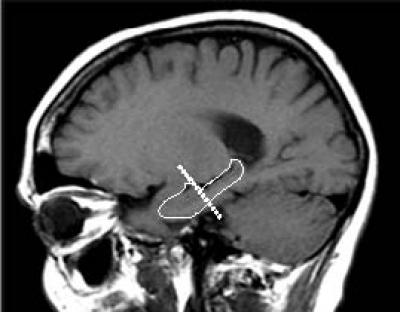

Previously, using high-resolution brain imaging, Dr. Small and his colleagues discovered that decreasing brain function in one area of the hippocampus, called the dentate gyrus, is a main contributor of normal decline in memory as we age.

This new study looked at measures that typically change during aging, like rising blood sugar, body mass index, cholesterol and insulin levels. The research found that decreasing activity in the dentate gyrus only correlated with levels of blood glucose.

"Showing for the first time that blood glucose selectively targets the dentate gyrus is not only our most conclusive finding, but it is the most important for 'normal' aging- that is hippocampal dysfunction that occurs in the absence of any disease states. There have been many proposed reasons for age-related hippocampal decline; this new study suggests that we may now know one of them," said Dr. Small.

The new findings also suggest that one way in which physical exercise could improve memory is via lowering glucose levels. Dr. Small's previous imaging studies in humans and in mice have documented that among all hippocampal subregions, physical exercise causes an improvement in dentate gyrus function.